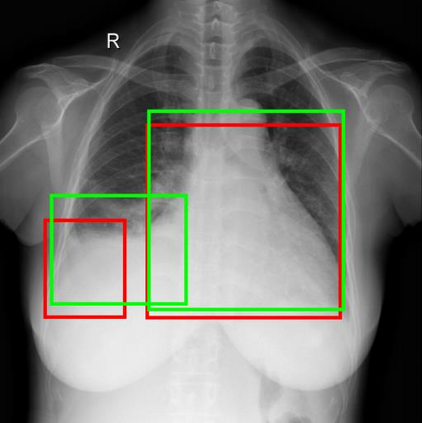

Chest X-ray (CXR) is the most typical diagnostic X-ray examination for screening various thoracic diseases. Automatically localizing lesions from CXR is promising for alleviating radiologists' reading burden. However, CXR datasets are often with massive image-level annotations and scarce lesion-level annotations, and more often, without annotations. Thus far, unifying different supervision granularities to develop thoracic disease detection algorithms has not been comprehensively addressed. In this paper, we present OXnet, the first deep omni-supervised thoracic disease detection network to our best knowledge that uses as much available supervision as possible for CXR diagnosis. We first introduce supervised learning via a one-stage detection model. Then, we inject a global classification head to the detection model and propose dual attention alignment to guide the global gradient to the local detection branch, which enables learning lesion detection from image-level annotations. We also impose intra-class compactness and inter-class separability with global prototype alignment to further enhance the global information learning. Moreover, we leverage a soft focal loss to distill the soft pseudo-labels of unlabeled data generated by a teacher model. Extensive experiments on a large-scale chest X-ray dataset show the proposed OXnet outperforms competitive methods with significant margins. Further, we investigate omni-supervision under various annotation granularities and corroborate OXnet is a promising choice to mitigate the plight of annotation shortage for medical image diagnosis.